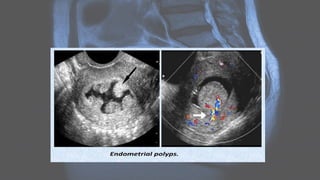

Ultrasound

• Ultrasound is usually the first imaging requested in a case of lower abdominal pain.

• Early findings in PID include :

• indistinct uterine margins

• echogenic pelvic fat

• fallopian tube thickening

Radiographic features Ultrasound • Ultrasoundis usually the first imaging requested in a case of lower abdominal pain. • Early findings in PID include : • indistinct uterine margins • echogenic pelvic fat • fallopian tube thickening